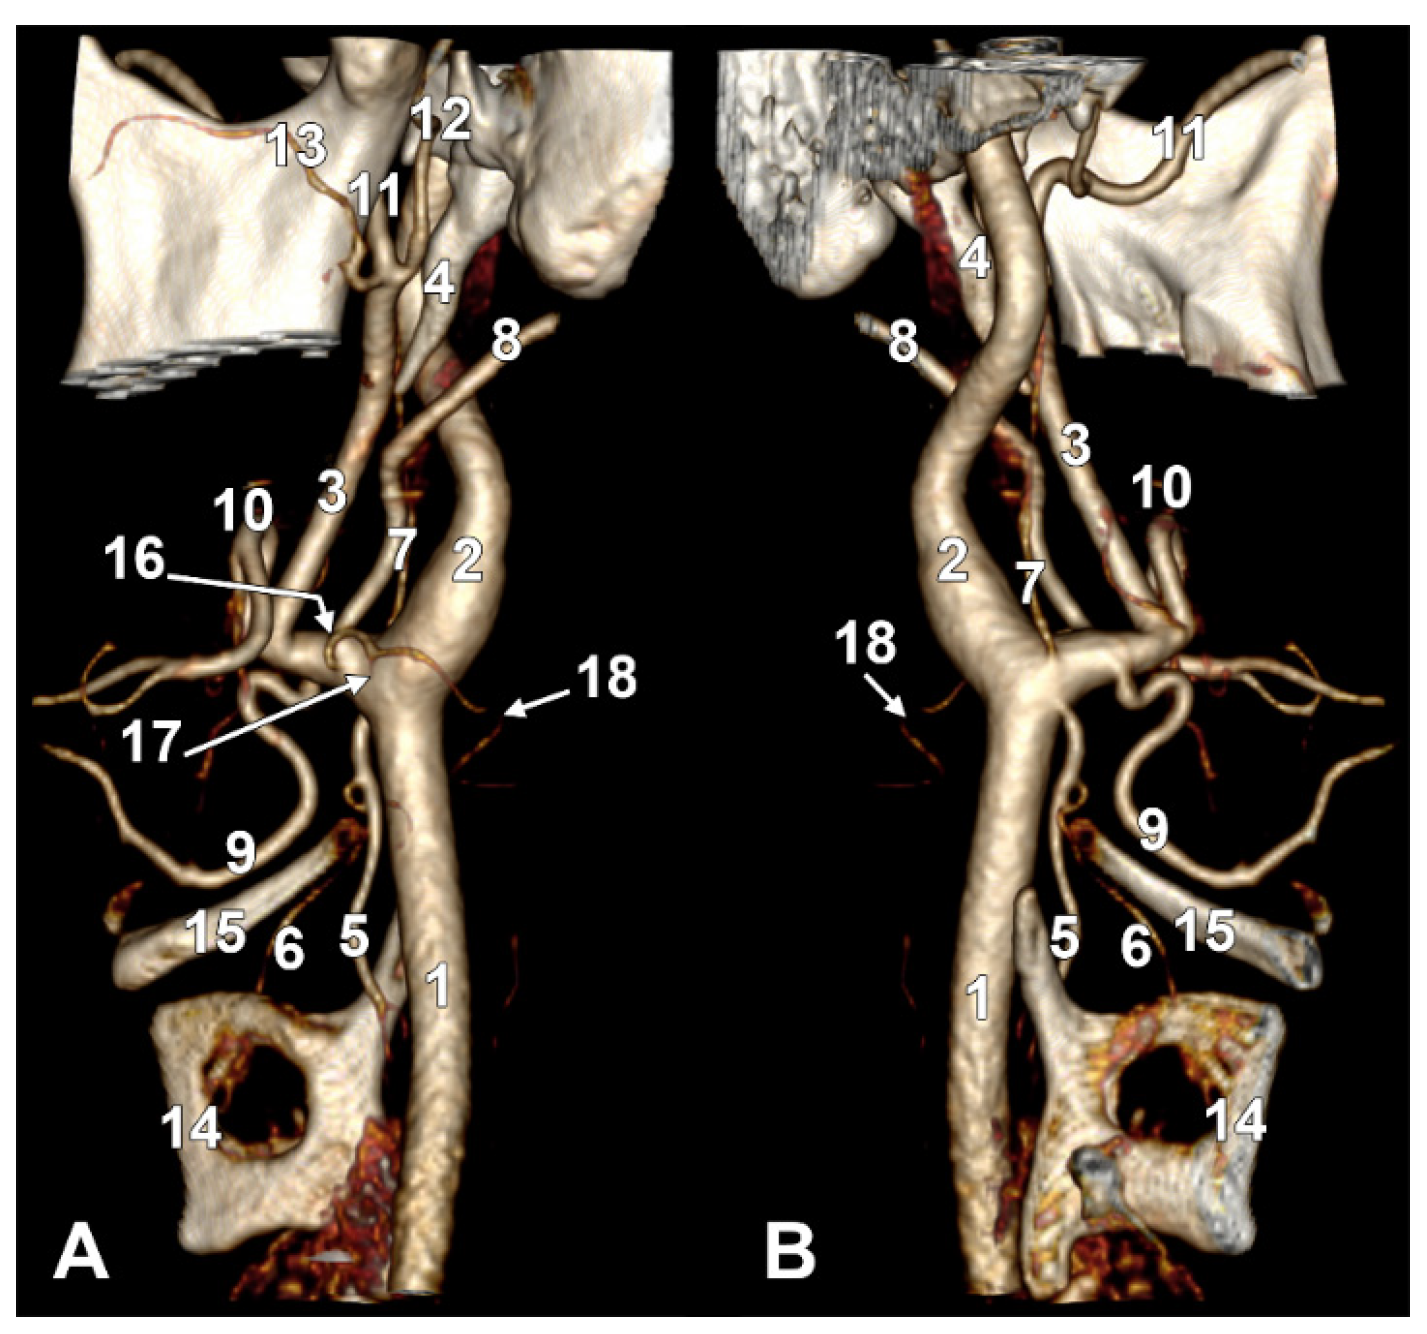

Figure 9. Thyrolingual trunk originating from the common carotid artery. The ascending pharyngeal artery is the first branch of the external carotid artery. Type 33 of the sequence of branches of the external carotid artery. Three-dimensional rendering. Left side. (A) Posteromedial view. (B) Antero-lateral view. 1. Common carotid artery; 2. greater hyoid horn; 3. thyrolingual trunk; 4. internal carotid artery; 5. ascending pharyngeal artery; 6. external carotid artery; 7. superior thyroid artery; 8. lingual artery; 9. facial artery; 10. styloid process; 11. ossified stylohyoid ligament.

On the left side (Figure 9), the APA originated 8.9 mm posterosuperior to the tip of the greater hyoid horn from the posterior wall of the origin of the ECA, as its first branch. This was because the LA and STA arose via a common TLT from the CCA. The TLT origin was 8.8 mm inferior to the greater hyoid horn; the length of this common arterial trunk was 5.1 mm. It divided at 5 mm lateral to the superior horn of the thyroid cartilage into two vertical branches—an upper one, the LA, which ascended over the greater hyoid horn and made an upper loop before continuing with the hyoglossal segment, and a second, inferior one, the STA.